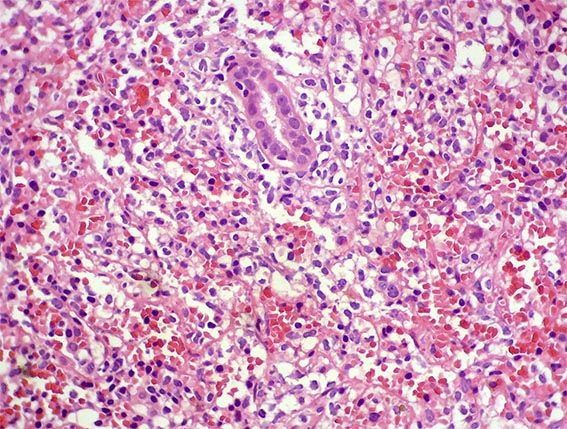

The patient is a 41-year-old woman with constitutional symptoms. Among the many studies undertaken to determine its cause, pyuria and microscopic hematuria were found in the urinary sediment, and, by ultrasonography, a ill-defined mass was evidenced on the renal upper pole of the left kidney.

A biopsy of the mass was obtained. See the images.

Figure 2. H&E, X400.